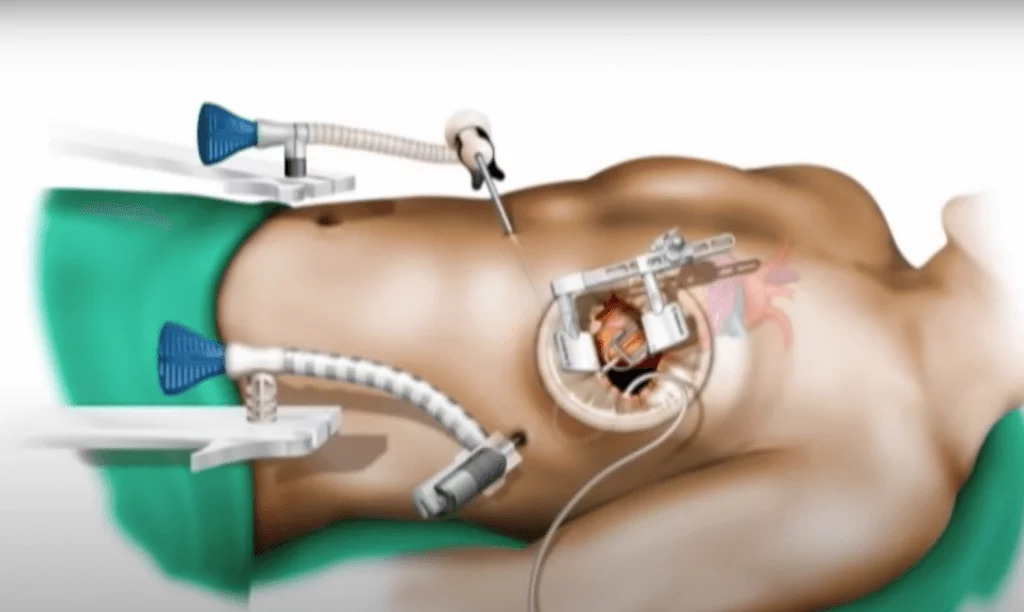

Minimal İnvaziv Kalp Cerrahisi Nedir?Minimal invaziv kalp cerrahisi, geleneksel açık kalp ameliyatlarına göre daha küçük kesilerle yapılan bir tedavi yöntemidir. Bu yöntem, dah